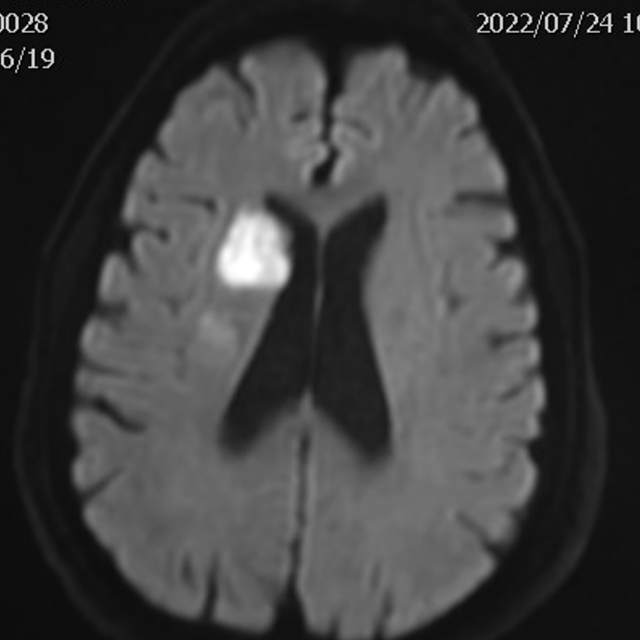

78岁老年男性,最近一个半月来已经和家里人没法正常交流,认知能力大幅下降,在农村,可能也就认为年龄大了,听天由命了。可老人家就是福大命大,有亲戚做医生,间隔17天先后为老人做了两次头颅MRI,发现脑梗塞,右侧血管长节段严重狭窄,右侧大脑半球缺血严重(图6,满江红),手术风险大……,家属经过反复咨询、犹豫、权衡,选择了保守治疗,毕竟老人年龄大了,手腿现在还能动,手术也有风险,时机也不是太好,国外研究不推荐,国内研究也不支持,保守治疗似乎是个不错的选择。然而,保守期间,患者反复出现脑梗塞,认知能力进行性下降,最终促使家属决定采用外科干预。然而,对医生而言,在梗塞的急性期处理这种长节段密布分支血管的病变风险不言而喻,而一味的观望和等候肯定不是最佳选择。过一点,可能出血;欠一点,可能闭塞。全面认真评估后,我们顺利为老人家完成了I期治疗,老人家的“火焰山”(图6)变成了“绿油油”充满生机的田野(图14),缺血明显改善,认知能力大幅提高,术后就能和家人正常交流了,也记起了很多以前忘记的事情……,家人很开心。